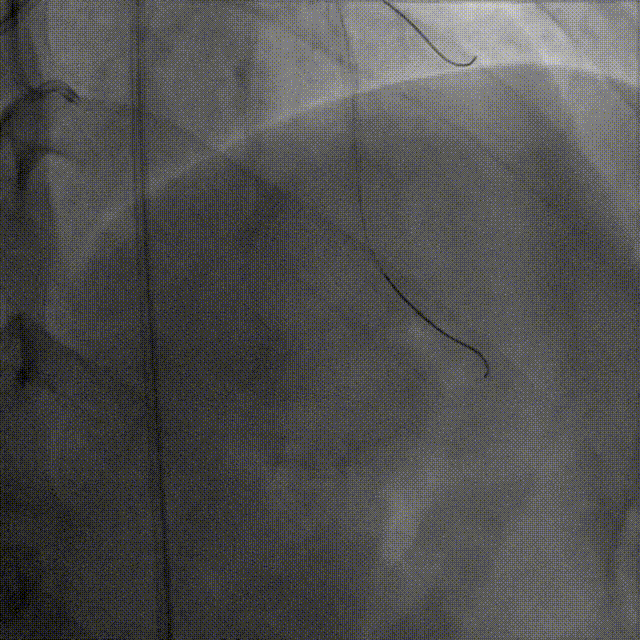

微导管高选择性造影(tip injection)显示远端心外膜侧枝迂曲

Caravel微导管支撑下,SUOH 03导丝通过心外膜侧枝送至LAD闭塞段远端

微导管“升级”通过侧枝

因侧枝血管严重迂曲,Caravel微导管无法通过侧枝,遂更换为1.5F HighTrack微导管顺利通过侧枝进入LAD远端

HighTrack微导管支撑逆向导丝前推至CTO病变体部,并跟进导丝进入CTO病变